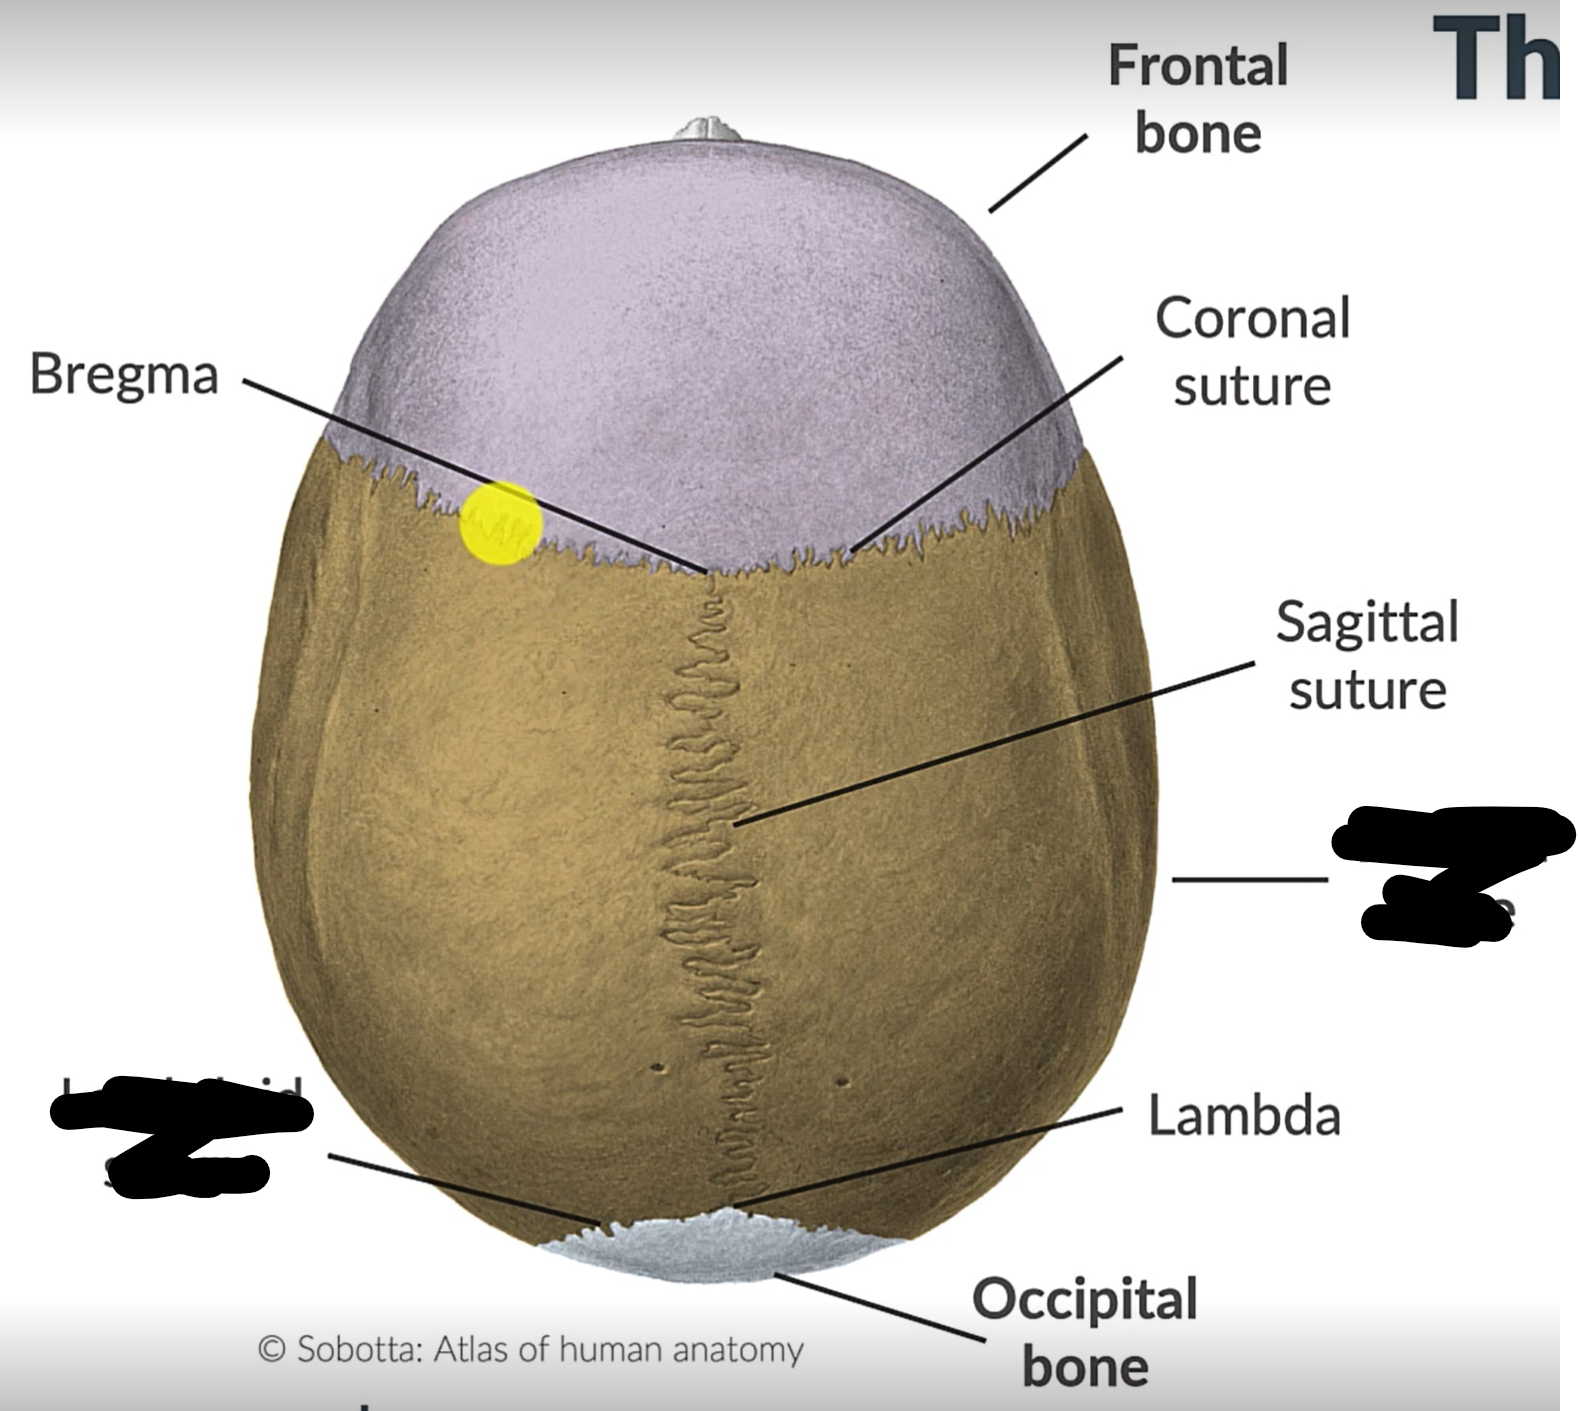

What are the 4 cranial sutures and what do they separate?

Lambdoid - separates occipital from parietal and temporal

Sagittal - extends between parietal bones

Coronal - divides frontal and parietal bones

Squamous - either side of cranium, separates temporal and parietal bones

What is the point where the frontal and parietal bones meet?

Bregma

Lambda